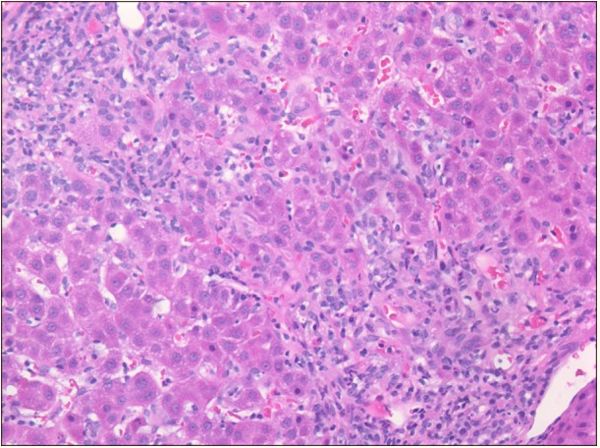

腹部超声多普勒超声检查:没有发现肝脏或胆道异常,但有轻微的脾肿大。肝脏活组织显示明显的玫瑰花结,浆细胞增多,窦状隙成熟淋巴细胞轻微增加,2期门静脉周围纤维化,无桥接或肝硬化结节,无嗜酸性粒细胞存在,无可染色铁、铜或A1AT小球。这些组织学发现与中度至重度急性慢性肝炎(总体3至4级)一致,提示自身免疫性肝炎。根据这些发现和整体临床表现,患者被诊断为继发于米诺环素的药物诱导的自身免疫性肝炎。

图1玫瑰花结和少量窦状成熟淋巴细胞

图2 血浆细胞增多